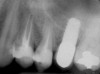

A full-thickness mucoperiosteal flap was raised, and alternating osteotomes were used to prepare the implant site. After achieving a length of 7 mm (Figure 7A and Figure 7B), heterologous bone graft was implanted and the osteotome sequence was repeated. The implant showed primary stability.

Figure 7A and Figure 7B Alternating osteotomes with variable conicity used to perform the alveolar remodeling in the area of tooth No. 15.